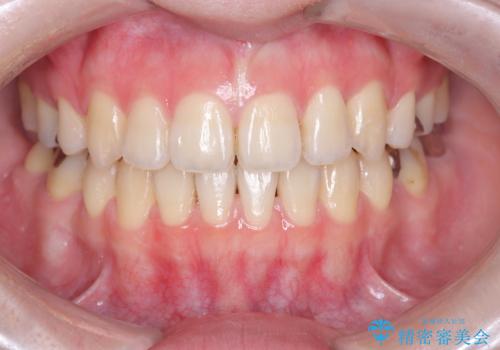

[ セラミック治療 ] 前歯の見た目を改善したい

![[ セラミック治療 ] 前歯の見た目を改善したいの症例 治療前](https://seimitsushinbi.jp/wp/wp-content/uploads/2025/10/IMG_9990-2-500x350.jpg?v=1761816440)

![[ セラミック治療 ] 前歯の見た目を改善したいの症例 治療後](https://seimitsushinbi.jp/wp/wp-content/uploads/2025/10/IMG_9934-500x350.jpg?v=1761816431)